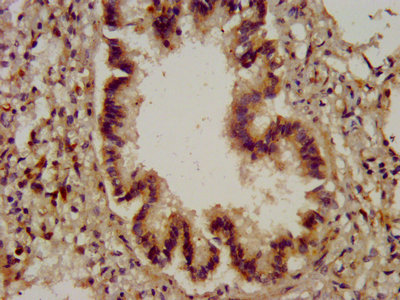

IHC image of CSB-PA006323LA01HU diluted at 1:200 and staining in paraffin-embedded human lymph node tissue performed on a Leica BondTM system. After dewaxing and hydration, antigen retrieval was mediated by high pressure in a citrate buffer (pH 6.0). Section was blocked with 10% normal goat serum 30min at RT. Then primary antibody (1% BSA) was incubated at 4°C overnight. The primary is detected by a biotinylated secondary antibody and visualized using an HRP conjugated SP system.

IHC image of CSB-PA006323LA01HU diluted at 1:200 and staining in paraffin-embedded human lung tissue performed on a Leica BondTM system. After dewaxing and hydration, antigen retrieval was mediated by high pressure in a citrate buffer (pH 6.0). Section was blocked with 10% normal goat serum 30min at RT. Then primary antibody (1% BSA) was incubated at 4°C overnight. The primary is detected by a biotinylated secondary antibody and visualized using an HRP conjugated SP system.